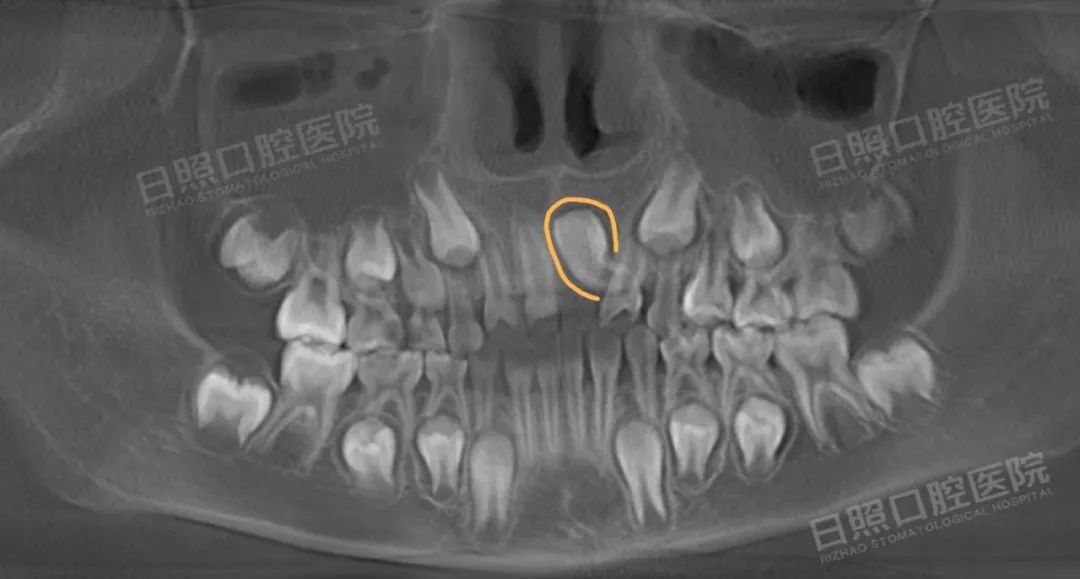

替牙列,21倒置埋伏阻生,多颗乳牙龋齿。

治疗前曲面断层片 黄圈处为倒置埋伏阻生牙